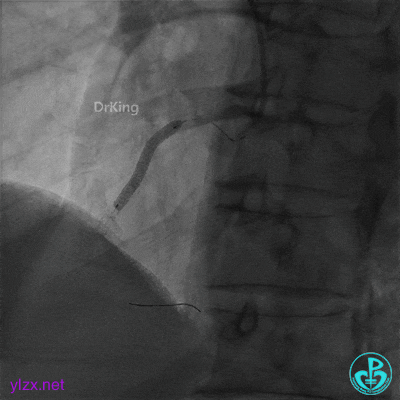

2.0×20mm球囊预扩张。

3.0×15mm双导丝球囊再次扩张。

双导丝球囊扩张后造影,血流缓慢,随即心率减慢至50次/分,血压降低至80/50mmHg,并出现短阵室速,随后意识丧失。